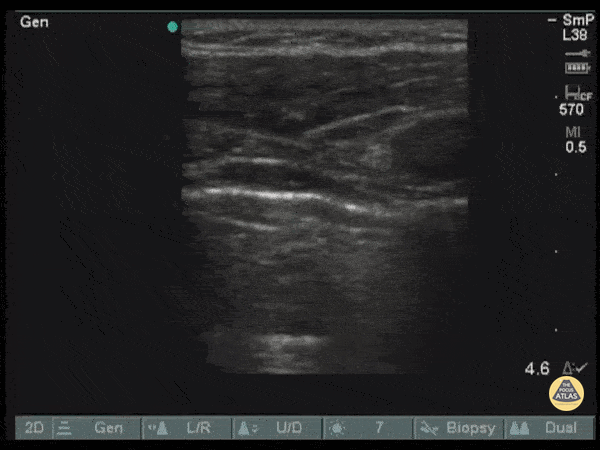

Pictured here is an amazing return of observable lung sliding as a pigtail catheter is advanced through. Reestablishment of lung sliding indicates lungs have re-expanded. Image courtesy of Robert Jones DO, FACEP @RJonesSonoEM Director, Emergency Ultrasound; MetroHealth Medical Center; Professor, Case Western Reserve Medical School, Cleveland, OH View his original post here